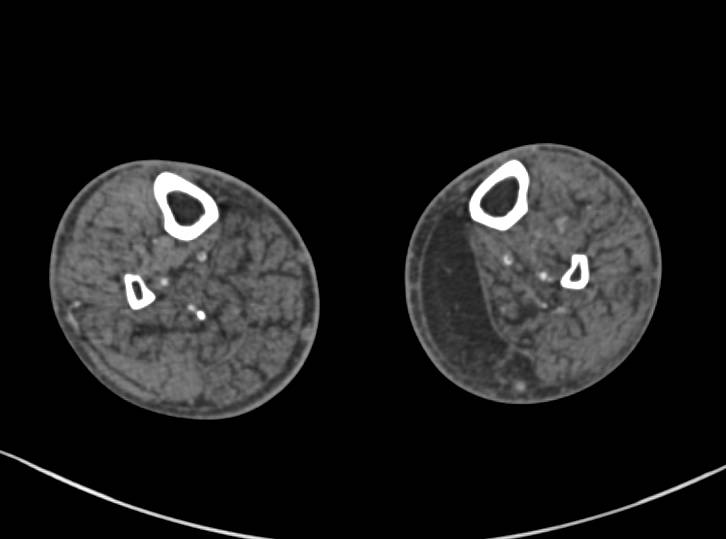

Atrophy of Medial Gastrocnemius Muscle to Trauma. Fractures of Tibia and Fibula Noted